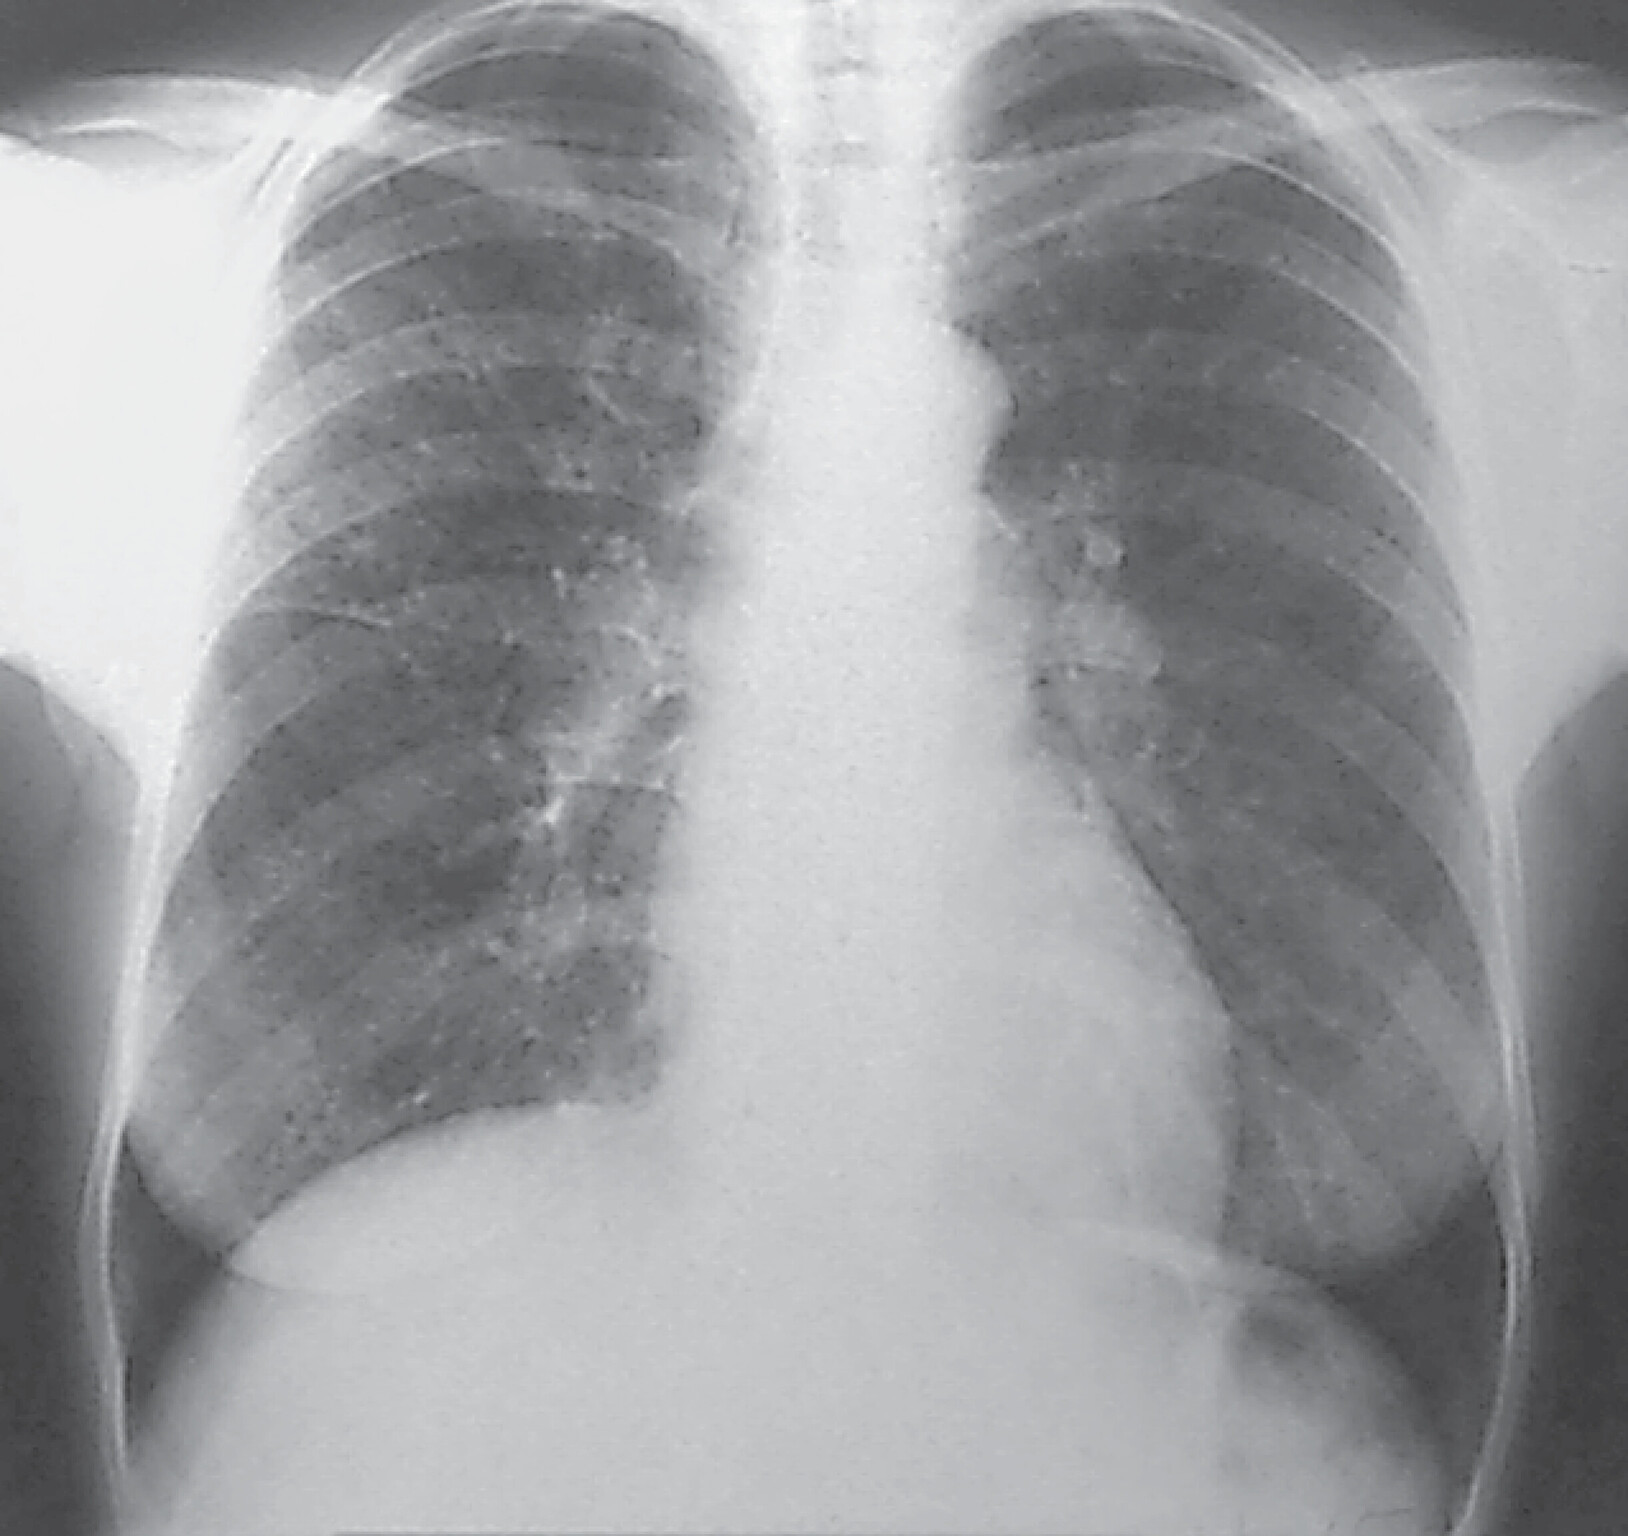

Diagnostik

Abb. 27.6 Silikose in der Röntgen-Thorax-Übersicht

Röntgen-Thorax-Übersicht p.–a.: Es kommen disseminierte, unterschiedlich große, relativ scharf begrenzte Fleckschatten in beiden Lungen zur Darstellung. Die Pleura ist abschnittsweise verbreitert.

(Quelle: Krombach G. Lunge und Pleura. In: Krombach G, Mahnken A, Hrsg. Radiologische Diagnostik Abdomen und Thorax. Stuttgart: Thieme; 2015)